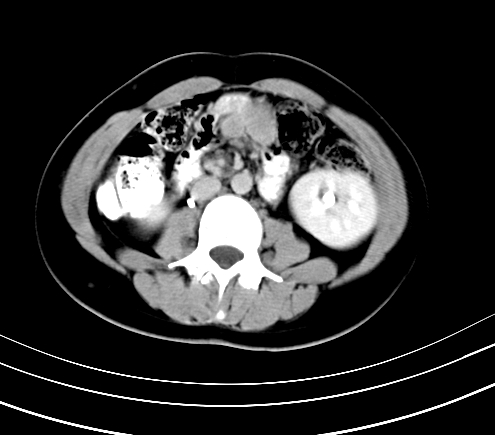

腹部平扫

静脉期